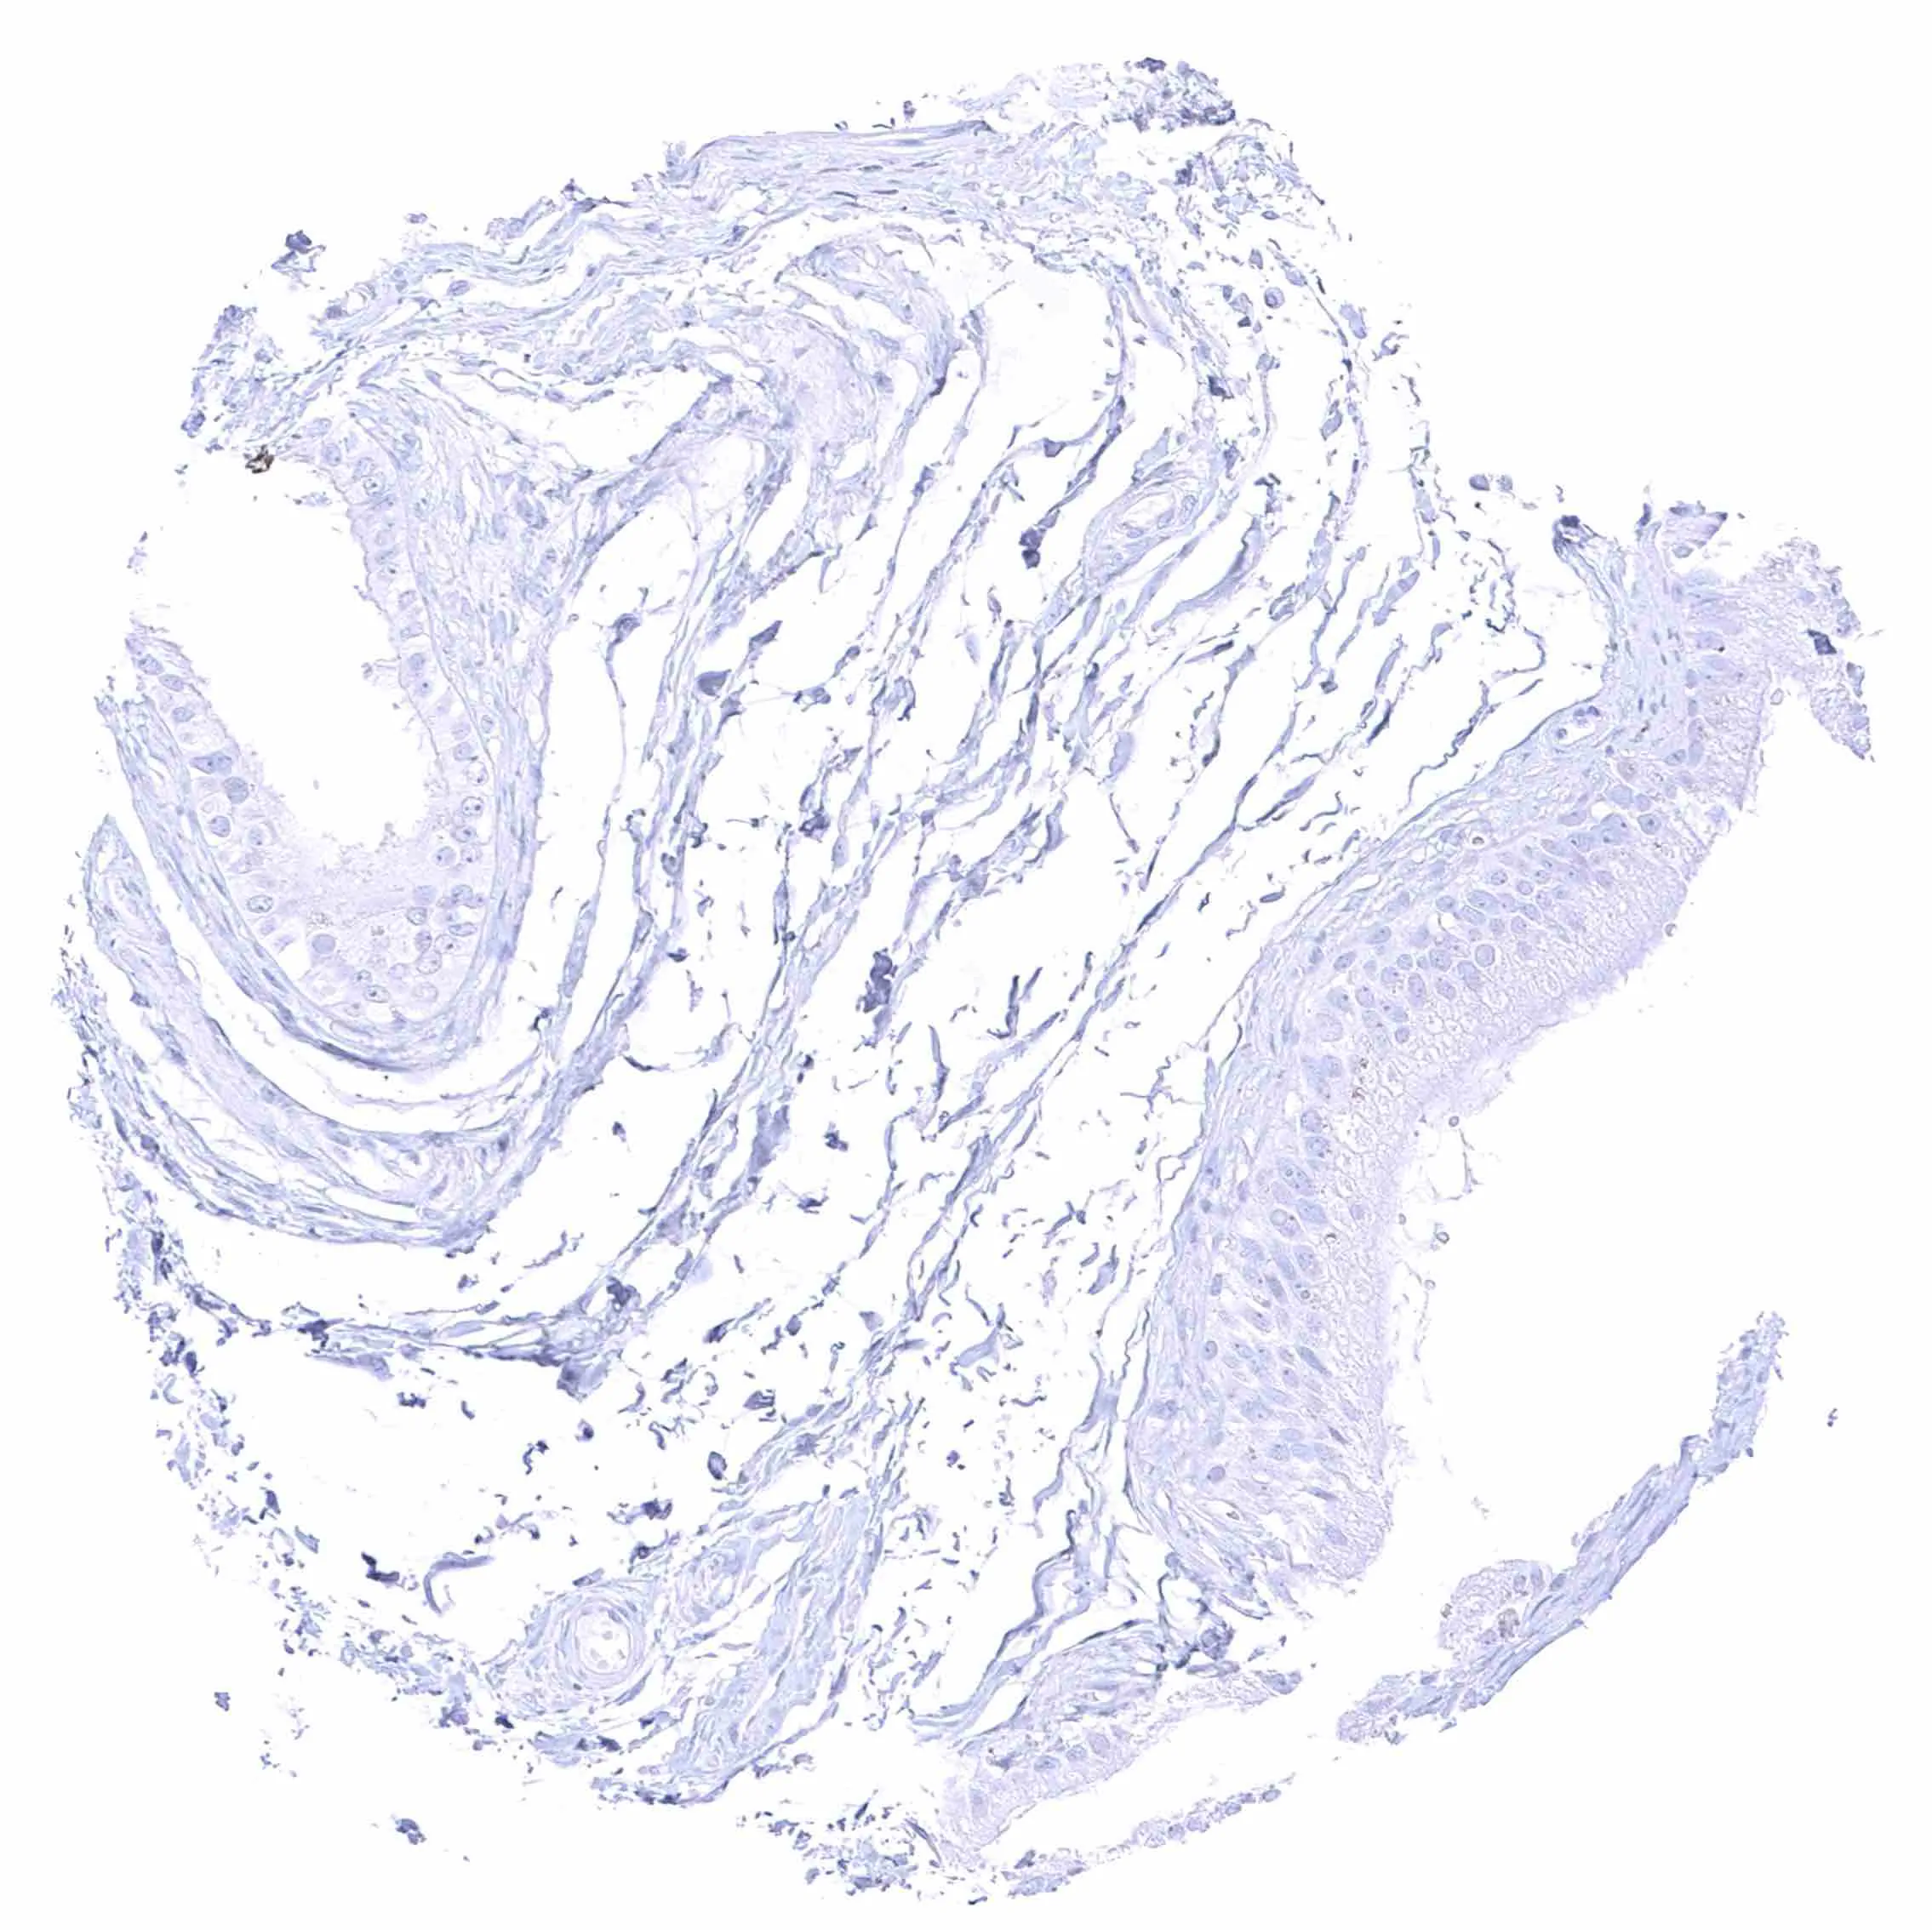

Skin, hairfollicel and sebaceous glands